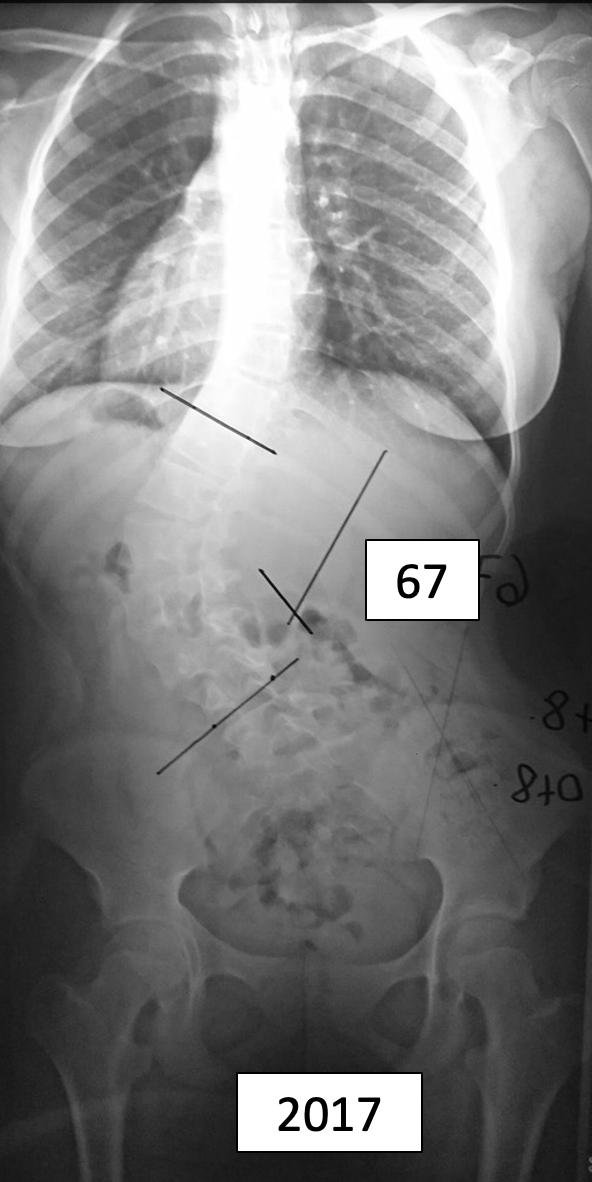

Marcela

DR. PABLO FIORILLO – Mat. 17034

Cirujano de Columna

Especialista en Escoliosis Pediatricos y Adultos